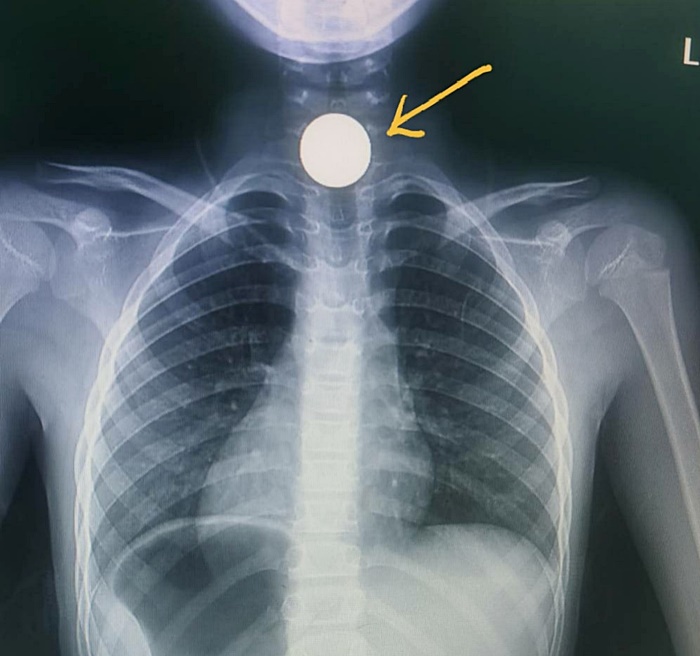

หมอเผยเคสอุทาหรณ์ผู้ปกครอง เด็ก 6 ขวบเล่นกับเพื่อน นำเหรียญ 5 บาท มาอมเล่น เผลอกลืนลงคอ กดทับหลอดอาหารจนเป็นแผลลึกเกือบทะลุ ต้องส่งผ่าตัดด่วน โชคดีทีมแพทย์ช่วยเหลือทัน เตือนเป็นเคสอันตรายถึงตายได้

โดย นพ.อารักษ์ ระบุว่า เด็กชายเล่นกับเพื่อน มีเหรียญ 5 บาทติดกระเป๋า จึงเอามาเข้าปากอมไว้เล่น ๆ ช่วงที่เล่นเพลิน ๆ เผลอกลืนลงไปจนติดคอ ยิ่งพยายามกลืนยิ่งเจ็บ ต้องทรุดตัวลงนั่ง อาเจียน น้ำลายไหลฟูมปาก พูดไม่ค่อยออก จนผู้ปกครองมาพบพาส่งโรงพยาบาลใกล้บ้าน แพทย์ฉุกเฉินเอกซเรย์เห็นเหรียญติดอยู่ที่คอส่วนบน แต่อยู่ลึกลงไปอ้าปากใช้ไฟฉายส่องมองไม่เห็นด้วยตาเปล่า ซึ่งตรวจอะไรมากไม่ได้เพราะเด็กมีอาการปวด จึงส่งต่อมาที่โรงพยาบาลสิชล และเตรียมส่งเข้าห้องผ่าตัดทันที

ระหว่างผ่าตัดแพทย์เห็นเหรียญติดค้างในแนวขวาง กดทับหลอดอาหารจนเป็นแผลลึกแต่ยังไม่ทะลุ จึงใช้เครื่องมือคีบดึงออกมาได้อย่างปลอดภัย หลังออกจากห้องผ่าตัด ได้ให้น้ำเกลือต่ออีก 1 วัน ให้ยาระงับปวด ยาปฏิชีวนะ เมื่อเห็นว่าเด็กไม่มีภาวะแทรกซ้อน เริ่มให้จิบน้ำ กินอาหารเหลว อาหารอ่อนได้